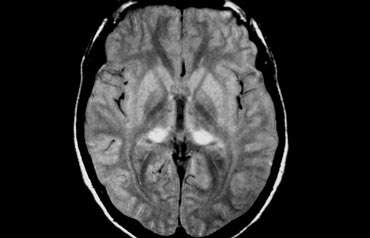

Cerebral Amyloid Angiopathy (CAA)

Dementia may be the clinical presentation in CAA, a condition in which ?-amyloid is deposited in the vessel walls of the brain.

The result is hemorrhage, usually microhemorrhages, but also subarachnoid hemorrhage or lobar hematomas may occur.

On MR, the T2* sequence will show multiple microhemorrhages, typically in a peripheral location (as opposed to hypertensive microhemorrhages, which are usually more centrally located, e.g. in the basal ganglia and thalami).

In addition, FLAIR will reveal moderate to sever white matter hyperintensities (Fazekas grade 2 or 3)

T2* images in a patient with CAA show multiple peripherally located microbleeds.

FLAIR images of the same patient show Fazekas 2 white matter hyprintensities.

T2* images in a patient with CAA microbleeds.

Cerebral Amyloid Angiopathy

T2* images demonstrate multiple lobar microbleeds in a patient with CAA.